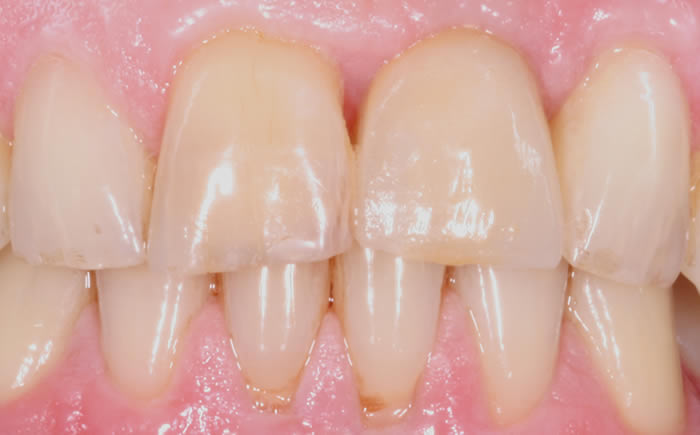

More front teeth replaced by dental implants

Case Three (4 images)